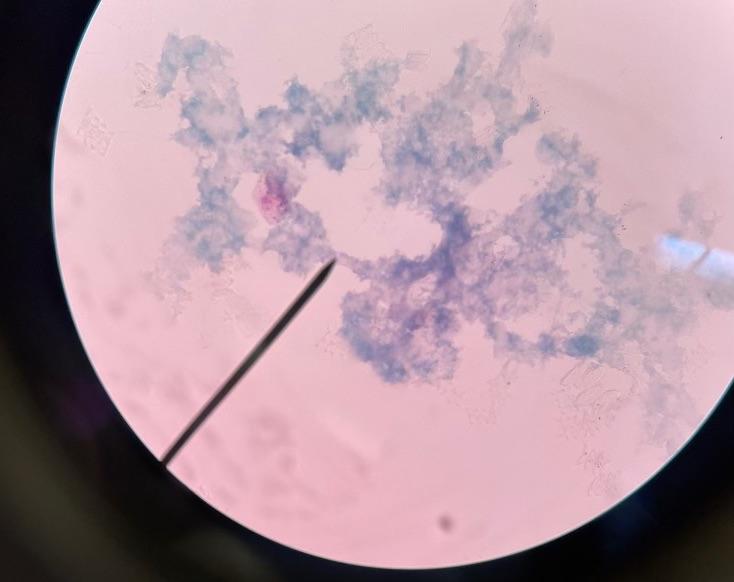

Plasmodium Vivax Blood Smear